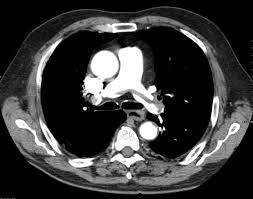

Aortic Dissection

Also known as thoracic aorta rupture, it occurs when you suffer a rupture or tear in the large blood vessel. The inner layer tear of the large blood vessel, which branches off the heart can result in the pain. The severe and sharp pain in the upper middle back can cause you agony. In such cases, you need to get emergency medical help. The problem is considered a medical emergency due to the severe complication associated with it.

Radiological studies include sophisticated imaging techniques that can offer a comprehensive view of the back region. It can detect the different underlying problems like cancer, injury, trauma or other issues triggering the pain. So, your doctor can suggest the following tests to detect the problem without any doubt:

The abdominal examination can detect the problems in your stomach as well as the small intestine. It will help detect the troubles in areas like esophagus or stomach using endoscopy. While ultrasound can determine problems with gallbladder. If the doctor suspects trouble with pancreas or liver, then a CT scan can provide comprehensive information.